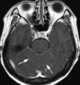

Carcinomatous infiltration

Leptomeningeal cancer (also called leptomeningeal carcinomatosis, leptomeningeal disease (LMD), leptomeningeal metastasis, neoplastic meningitis, meningeal metastasis and meningeal carcinomatosis) is a rare complication of cancer in which the disease spreads from the original tumor site to the meninges surrounding the brain and spinal cord. This leads to an inflammatory response, hence the alternative names neoplastic meningitis (NM), malignant meningitis, or carcinomatous meningitis. [Source: Wikipedia ]